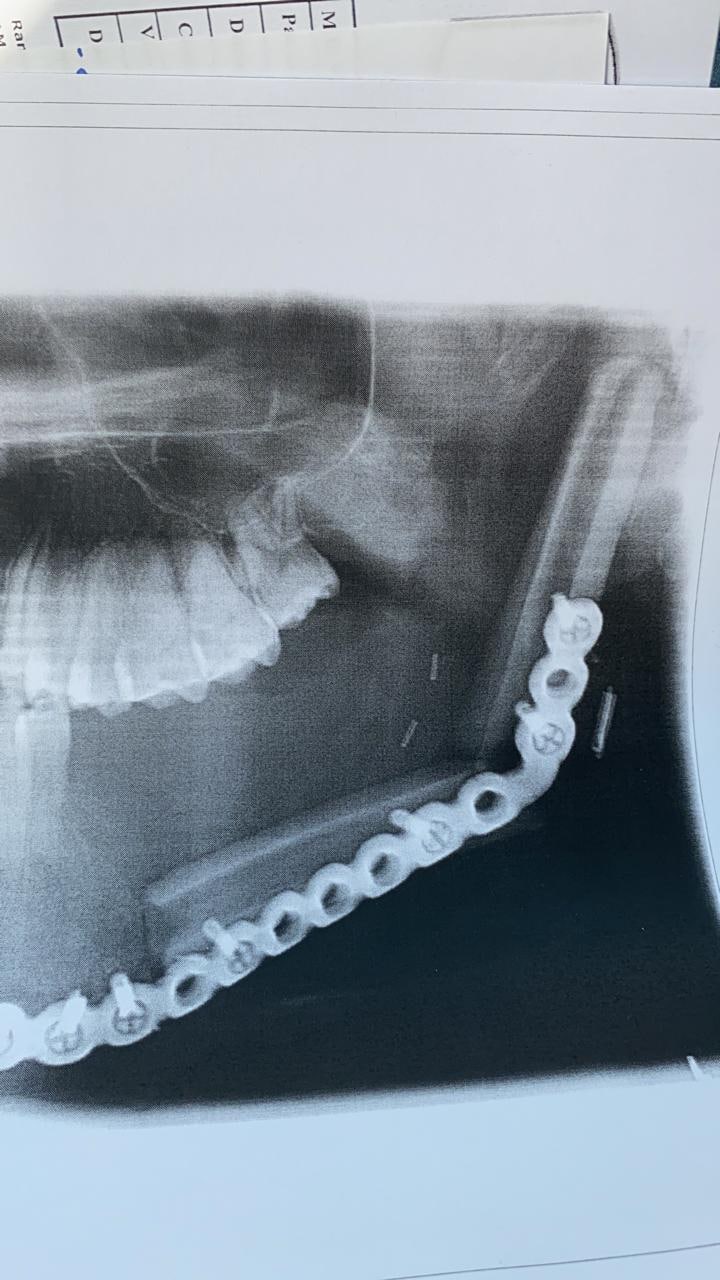

وكان المريض يعاني من وجود ورم في الفك الأيسر أدى إلى تآكل جزء كبير من عظمة الفك وبعد عمل الأشعة والفحوصات اللازمة ودراسة الحالة وعمل الإجراءات لتجهيز المريض إلى غرفة العمليات لترميم الفك المتآكل قام الفريق بإجراء العملية استمرت أكثر من 10 ساعات متواصلة لحصد جزء من عظام الساق مع الشرايين والأوردة الخاصة به عن طريق جراحة ميكروسكوبيه معقدة, ثم إعادة تشكيل هذا الجزء من العظام ليماثل الجزء المستأصل من عظام الفك وتثبيته بشرائح معدنية للحفاظ على شكله الجديد واستعادة وظيفته الأساسية, وعاد المريض ولله الحمد لممارسة حياته بصورة طبيعية.